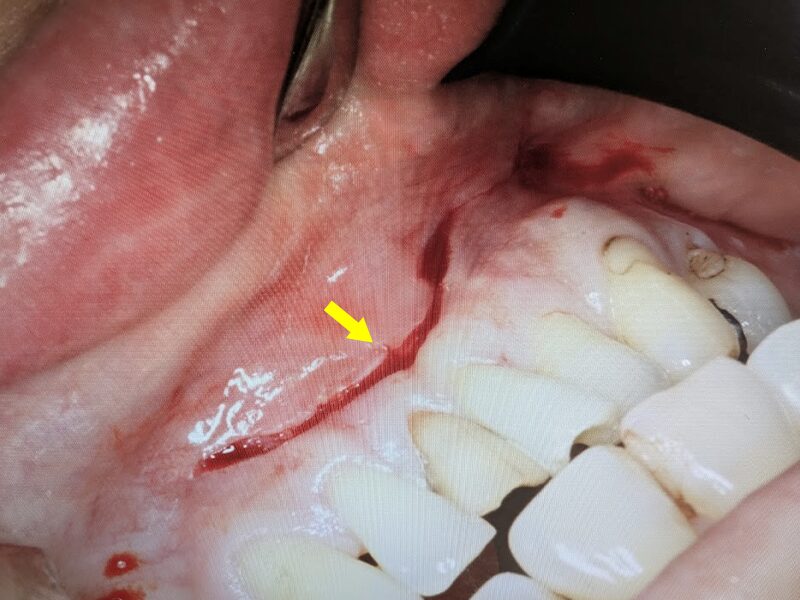

切開を実施いたします。

歯肉粘膜骨膜弁を剥離していきます。嚢胞壁は骨膜と癒着していため、鈍的に剥離を進めます。できるだけ嚢胞壁を壊さないようにします。